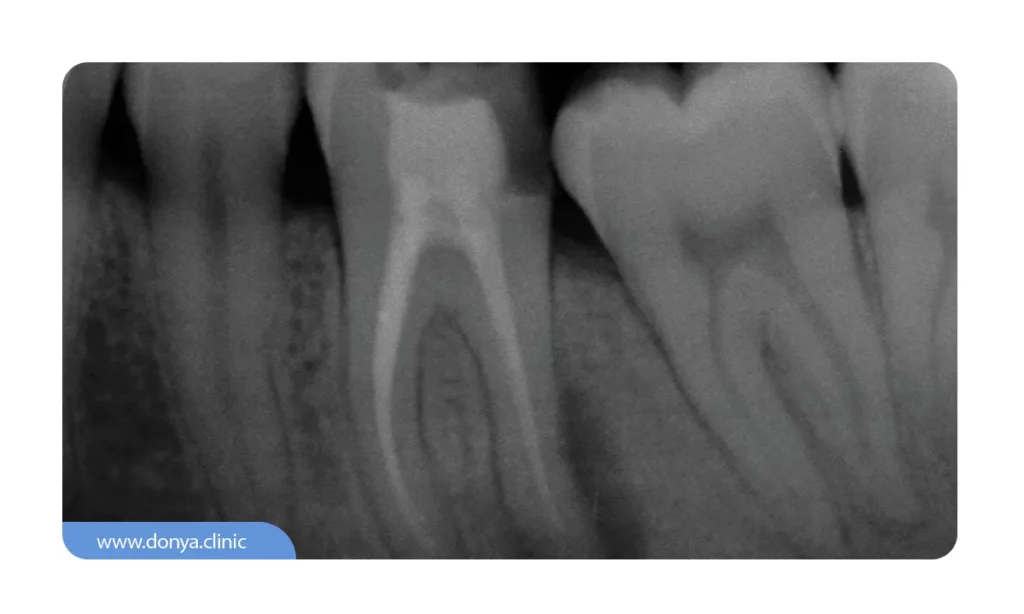

3️⃣ عکس دندان Periapical (رادیوگرافی پری اپیکال)

رادیوگرافی پری اپیکال به دندانپزشک در ارزیابی وضعیت سلامت 1 ال 2 دندان اطراف دندان دچار صدمی دیدگی کمک بسزایی می کند. در تصویربرداری پری اپیکال ارتفاع کلی ساختار متشکل یک واحد دندانی (از پایین ترین نقطه یا ریشه دندان تا بالاترین نقطه یا عاج) مشخص است.

دندانپزشکان ممکن است در وضعیت یک دندان خاص قبل از اجرای فرآیندهای درمانی نظیر استخراج آن یا پر کردن دچار تردید و شک شوند؛ محتویات و جزئیات این عکس به متخصصان کمک می کنند تا از وضعیت سلامت واحد دندانی مذکور کسب اطمینان کنند.

💵 هزینه عکس دندان پری اپیکال در سال 1404 برای تک دندان از 90 هزار تومان و برای دو دندان از 100 هزار تومان شروع می شود.